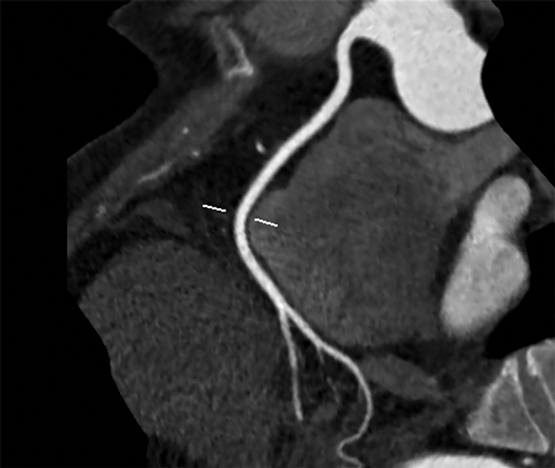

Clinical vignette 1: A 55-year-old woman presents to her general practitioner with dyspnoea on exertion, and risk factors of obesity and hypertension. A nuclear single-photon emission computed tomography myocardial perfusion scan is reported as positive for “mild apical ischaemia”. Computed tomography coronary angiography (CTCA) is performed to exclude significant coronary artery disease, demonstrating no significant stenosis in the major epicardial coronaries (left anterior descending, left circumflex or right coronary artery), but mild diffuse coronary atherosclerosis is present (with a calcium score of 370 Agatston units). She is commenced on medical therapy of aspirin and a statin, and is reassured that she does not have a stenosis requiring stent or bypass surgery, and that her chest symptoms are not due to coronary artery disease.

CTCA showing “clean” coronary arteries with no plaque or stenosis.